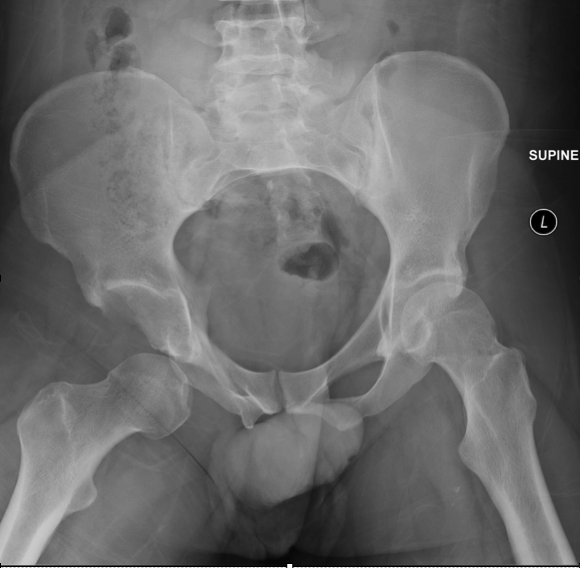

skiing accident, hip ROM limited, right leg shortened & internally rotated

posterior hip dislocation (posterior & inferior displacement of femoral head)